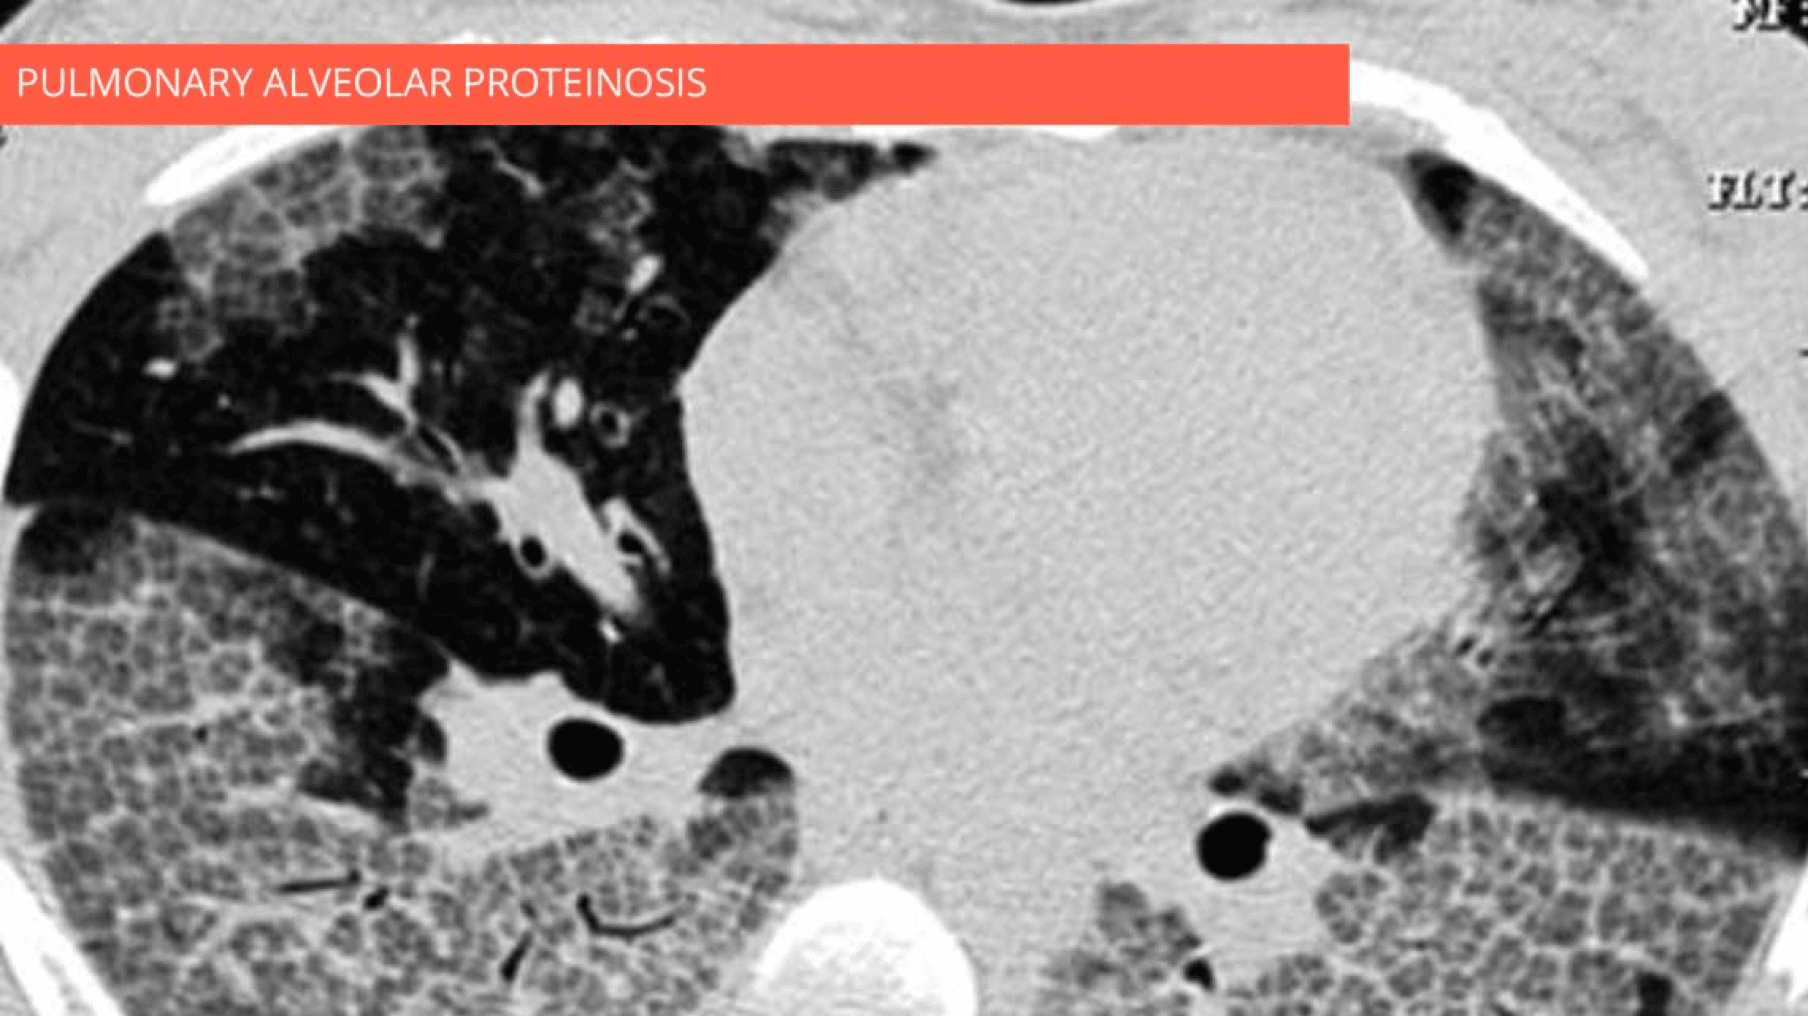

Combination of ground-glass opacity, thickened polygonal septal lines, and intralobular reticulations predominantly in the lower lobes. Note the spatial heterogeneity of lesions.

•  Combination of ground-glass opacity, thickened polygonal septal lines, and intralobular reticulation